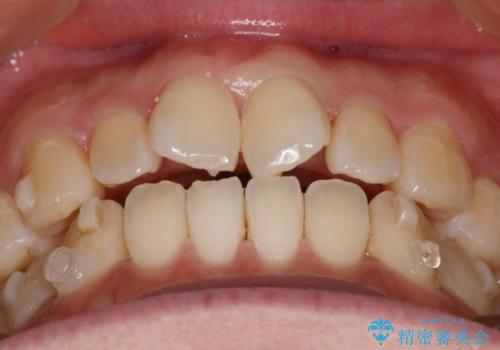

- 上の前歯の捻れを主訴に来院されました。

前歯の捻れとがたつきを改善するために、IPR(歯と歯の間を削る処置)と歯列拡大をすることで歯並びを整えていく治療計画を立てました。

かみ合わせを整えるためにゴム掛けも行いながら、治療していきました。

患者様にマウスピースの使用とゴム掛けを頑張っていただいたおかげでリファイメント(マウスピースの再発注)も1回で終了することができました。